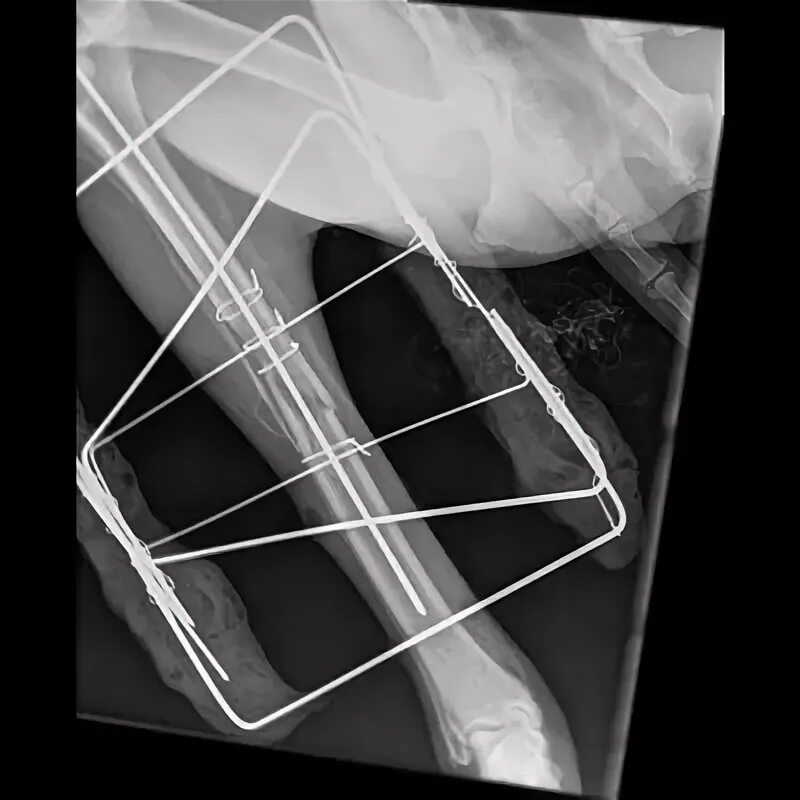

Остеосинтез мрт